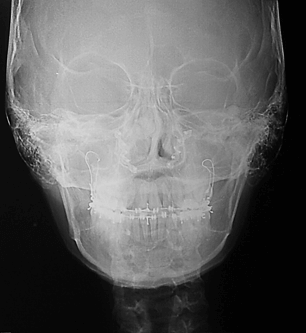

Radiografía Postero Anterior Inicial

Donde se puede evidenciar la marcada asimetría facial e hiperplasia condilar izquierda.